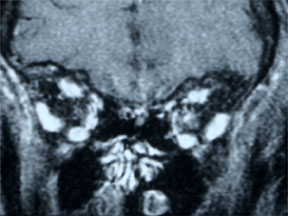

- 左眼视神经增强伴颅内蔓延,病损累及第二视神经 (图 3, 4 ,5)

- 符合视神经脑膜瘤的表现

- 肿瘤可能起源于眶内的视神经鞘膜在颅内孔处,向颅内生长